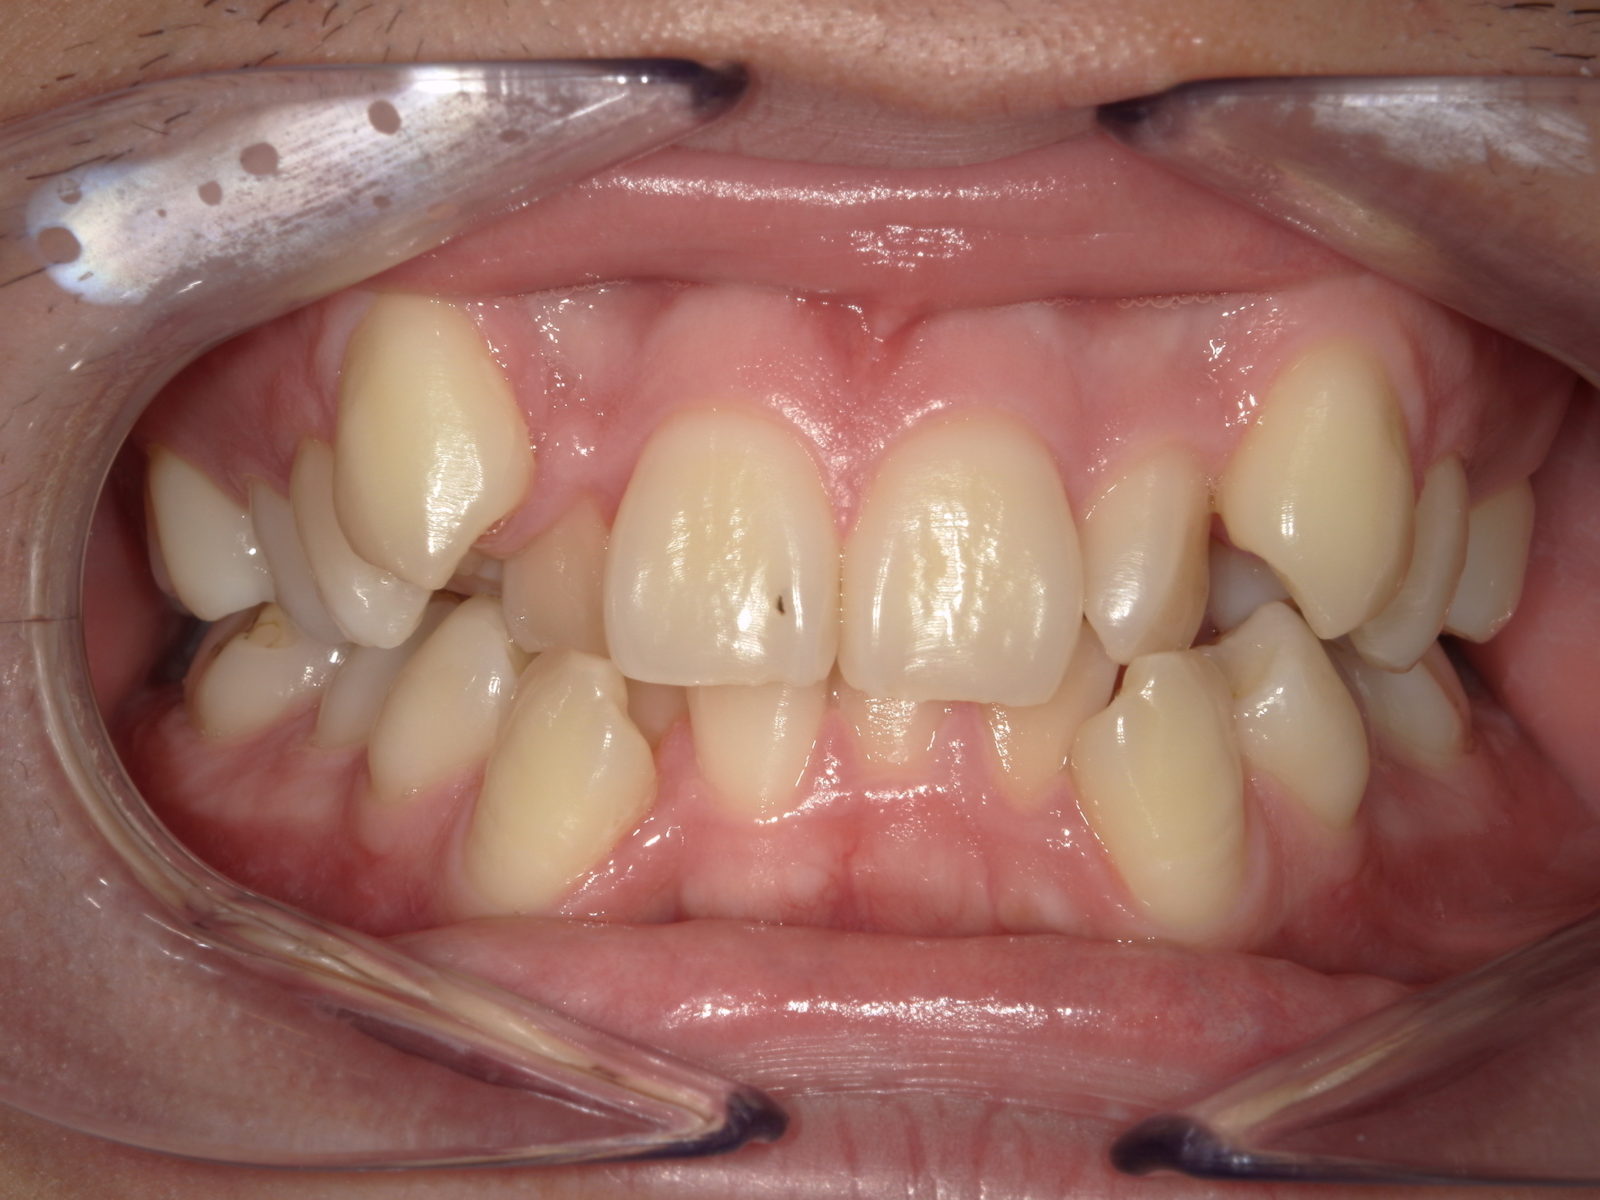

【主訴】歯のガタつき

【診断結果】叢生

【治療開始時の年齢】32歳

【治療内容】マウスピース型 (カスタムメイド) 矯正装置

【抜歯部位】上下左右4番目

【治療経過】後戻り無

【治療期間】2年4ヶ月

【治療費用】937,200円

【リスク・副作用】

治療初期の段階では痛みや不快感が生じる可能性がある。適切に歯磨きをしないと虫歯になる可能性が高くなる。個人差により予想された治療期間より長くなる場合がある。治療後はリテーナーを装着しないと後戻りしてしまうリスクがある。